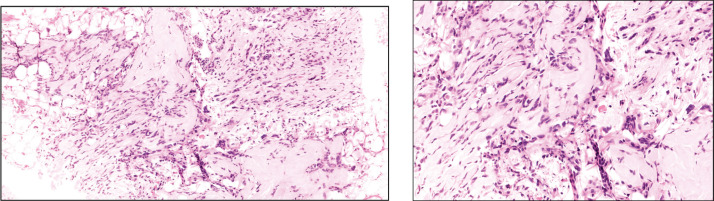

With the advent of next-generation sequencing, increasingly we can sub classify the soft tissue sarcomas into various subtypes with distinct prognostic and therapeutic implications. Sarcomas with RAF1 mutations are extremely rare and so far, the treatment strategies are not known. Here, we report a case of a 48-year-old lady who initially presented with right ear swelling, which was excised and was suggestive of dermatofibrosarcoma protuberans with S100 expression. After a disease-free interval of 25 months, the patient relapsed with metastasis in the lung. Repeat biopsy and next-generation sequencing (NGS) were suggestive of PDZRN3/RAF1 fusion mutated sarcoma. On presentation, the patient had an Eastern Cooperative Oncology Group performance status of 4 and had respiratory distress due to lung metastasis. After consensus and decision in the molecular tumour board, the patient was started on low-dose trametinib and doxorubicin. After three cycles of treatment, the patient had a partial response and post six cycles she had a near-complete response. This case exemplifies the value of molecular characterisation of soft tissue sarcoma and adds to the already sparse literature for RAF1 mutated sarcomas.

Abstract Image